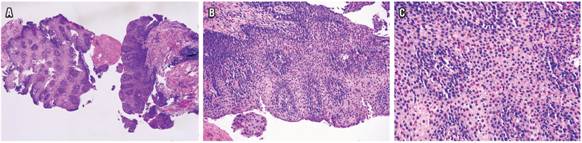

Con el estudio histológico del tejido esofágico, en 24 pacientes (52,17 %) se encontró un conteo de eosinófilos por CAP de 15 a 40, 41 a 60 en 9 pacientes (19,56 %), 61 a 80 en 7 pacientes (15,21 %), 81 a 100 en 1 paciente (2,17 %) y más de 100 eosinófilos por CAP en 5 pacientes (10,86 %). Los hallazgos histológicos adicionales más frecuentes fueron hiperplasia de la lámina basal en 44 pacientes (95,65 %), acantosis en 14 pacientes (30,43 %) y degranulación eosinofílica en 12 pacientes (26,08 %) (Figura 2 , Tabla 3).

La presentación histológica de la EEo compromete todos los componentes tisulares representados en una biopsia. El epitelio puede verse acantósico debido a la expansión de la zona basal, la que puede corresponder a la totalidad del engrosamiento epitelial. La presencia de células inflamatorias intraepiteliales, en este caso eosinófilos, corresponde a la respuesta de células T ayudantes de tipo 2 (Th2) frente a los antígenos deglutidos 35. Además de la alteración numérica, los eosinófilos suelen presentarse con distribución anómala, en forma de exudado luminal y formación de microabscesos con exudado; o en el epitelio intacto, tapizando la superficie; o por el contrario, concentrarse más predominantemente en la lámina propia. Es posible observar degranulación de eosinófilos, posiblemente secundaria a disrupción celular mecánica 35. En contraste con la histología de una lámina propia normal, en los casos de EEo, sus fibras suelen estar engrosadas y densas 36, puede verse comprometida por inflamación eosinofílica crónica 18 y algunas veces con numerosas células plasmáticas 35.

De este modo, los hallazgos histológicos más frecuentemente descritos entre los pacientes de esta cohorte fueron la hiperplasia de la lámina basal, acantosis y degranulación de eosinófilos. Otros cambios como la elongación papilar y la formación de microabscesos fueron menos frecuentes. De manera interesante, en 31 pacientes (67 %) la biopsia gástrica mostró características histológicas compatibles con gastritis crónica, y en 10 de los pacientes (32 %) se observaron bacilos compatibles con H. pylori.